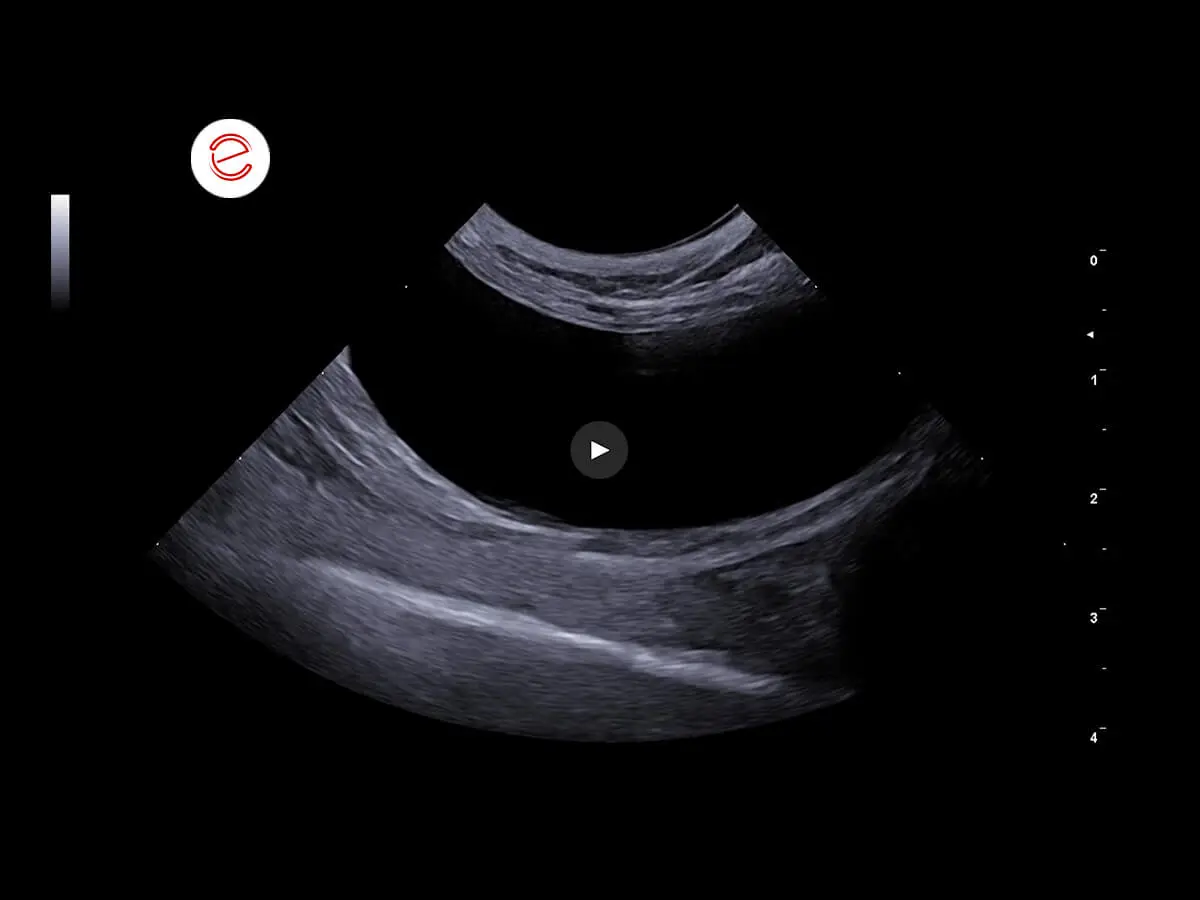

Left kidney: normal size, irregular margins, cortical hyperechogenicity, loss of cortico-medullary distinction. In the pyelic recesses, various hyperechoic areas were shown, forming a posterior shadow cone.